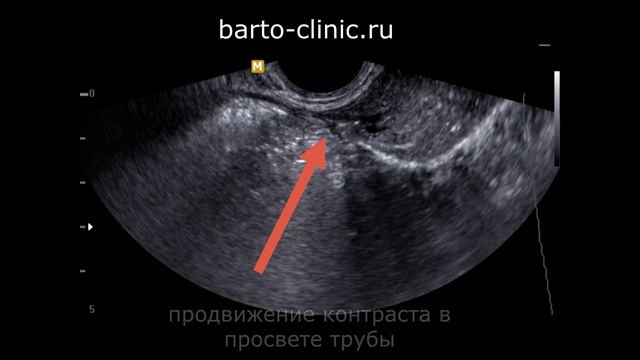

Гистеросальпингография, или соногистерография и проходимость маточных труб. Внимание! Есть противопоказания. Требуется консультация врача. Запишитесь на консультацию в ЦИР https://clck.ru/3RKvZc Вступайте в наш чат в Телеграме https://t.me/+oSFphhZ3MMo4YmIy В этом видео Воеводин Фёдор Сергеевич, врач ультразвуковой диагностики Центра иммунологии и репродукции, рассказывает про соногистерографию, или сальпингогистерографию, или гистеросальпингографию. Это три названия одного и того же исследования. Среди причин женского бесплодия примерно 25-30%, по статистике, приходится на так называемый трубный фактор. Трубный фактор - это нарушение движения яйцеклетки по маточным трубам. То есть, яйцеклетка созревает в одном из яичников и начинает двигаться по соответствующей трубе в сторону полости матки. По мере движения она встречает сперматозоиды, происходит оплодотворение, и оплодотворённая яйцеклетка уже должна попадать в полость матки, прикрепляться, и беременность должна развиваться. Но если беременность не наступает, а сам факт овуляции, то есть созревания и выхода яйцеклетки из яичника, с помощью врачей, установлен, то возникает вопрос, собственно, в проходимости маточной трубы. Причин нарушения проходимости маточных труб может быть несколько. Они могут быть как врождённые, то есть какие-то анатомические врождённые особенности, так и приобретённые - вследствие каких-то воспалительных процессов, то есть, инфекционного характера или как следствие оперативных вмешательств. Также в качестве причин может быть эндометриоз. Проверить проходимость труб можно несколькими способами. Во-первых, это забеременеть. То есть, если беременность наступила, даже если она потом оказалась неудачной, то мы понимаем, что та труба со стороны яичника которой выходила яйцеклетка, проходима. Второй вариант - проверить это интрооперационно, или одновременно с проведением какой-то гинекологической операции. То есть, хирурги могут ввести в полость матки физиологический раствор и непосредственно глазами проконтролировать его прохождение по обеим маточным трубам. Но если беременность не наступает, овуляция чётко происходит, а никакие оперативные вмешательства не планируются, то тогда есть такой вариант, как соногистерография или, как я уже сказал, сальпингогистерография, в двух форматах: либо под контролем ультразвука, либо под контролем рентгена. Ну, в данном случае мы в этом видео будем рассматривать вариант под контролем ультразвука. Тем более, что у него есть некоторые преимущества перед рентгеном. О них мы тоже поговорим. Досмотрите это видео до конца! Мы во Вконтакте https://vk.com/socialnetcir Наш Рутуб https://rutube.ru/channel/23913594/ Наш Яндекс Дзен https://vk.cc/cc19Fc Центр иммунологии и репродукции (ЦИР) - cеть клиник фертильности, акушерства и пренатальной диагностики с собственной лабораторией медицинских анализов "Лаборатории ЦИР". Работаем с 1996 года. Основные направления деятельности: - диагностика и лечение бесплодия и невынашивания беременности - подготовка к ЭКО - планирование беременности и ведение беременности - урология и андрология - помощь и профилактика тяжелых осложнений беременности, преэклампсии, АФС, тромбофилии - все виды анализов. Мы помогаем людям стать родителями даже в самых сложных случаях! Наш канал посвящён акушерству, гинекологии и репродуктивной медицине. Мы публикуем видео о новостях медицины, обзоры статей из зарубежных научных журналов, разборы сложных клинических случаев, а также отвечаем в наших видео на вопросы подписчиков. Наши видео будут полезны как для врачей разных специальностей, чья работа связана с репродуктивной медициной, так и для пациентов и для широкого круга людей интересующихся акушерством и гинекологией и ищущих ответы на свои вопросы. На нашем канале проходят прямые трансляции с кандидатом медицинских наук, врачом акушером-гинекологом, Гузовым Игорем Ивановичем, в которых он рассказывает о новостях медицины и отвечает на ваши вопросы. Подпишитесь на наш канал, чтоб не пропустить трансляции и выход новых видео! Это видео в Ютубе https://youtu.be/kE-IAQpDKOQ #ЦИР #ВоеводинФС #соногистерография #сальпингогистерография #гистеросальпингография